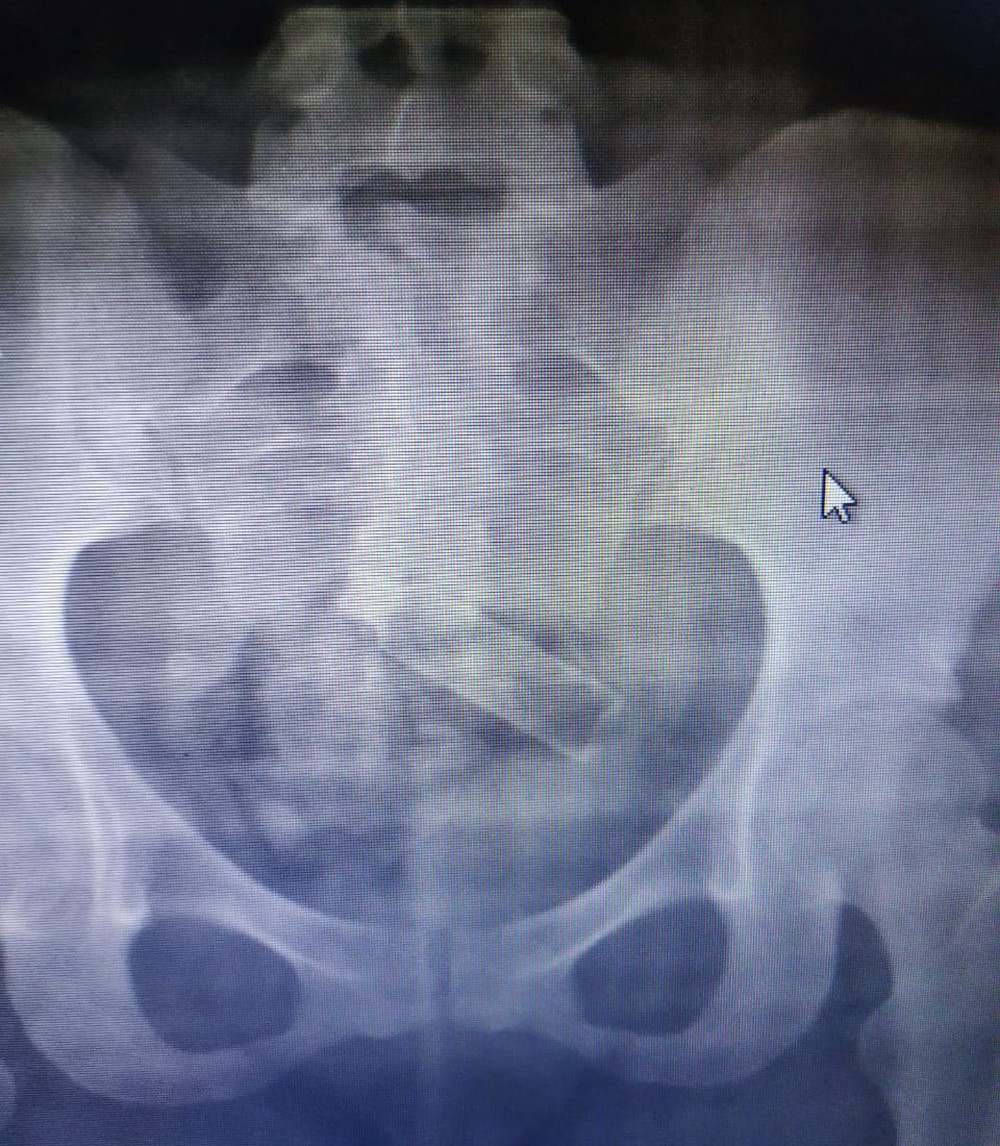

Os agentes a levaram para o HUT, onde foi feito um raio X e constatou somente um vidro de perfume. Ao passar pela tomografia teve-se a certeza que existia a droga. 50 gramas de maconha e o vidro de perfume estavam envolvidos em um saco plástico.